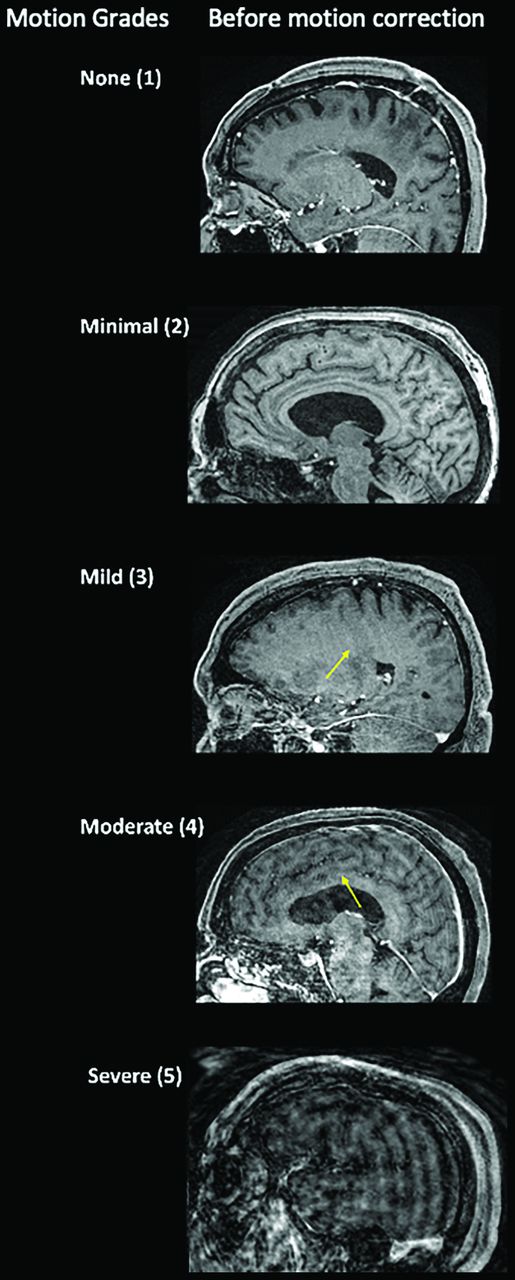

Two neuroradiologists (M.L. and J.F. with 3 and 5 years of experience, respectively) performed independent blinded reviews of unlabeled MPRAGE images without and with SAMER motion correction. The order of the study and the type of study (baseline-versus-SAMER motion-corrected images) were randomized by A.T. for the reviewing neuroradiologists. Cases with any discrepant grades were adjudicated independently by a third blinded senior neuroradiologist (J.C.) with >10 years of experience. A previously established 5-point motion scale was used for grading (Fig 1).1 Grade 1 indicates the absence of detectable motion artifacts; grade 2 indicates minimal motion with barely detectable motion artifacts and a negligible effect on image quality and diagnosis; grade 3 indicates mild motion with noticeable motion artifacts that likely do not have diagnostic consequences; grade 4 indicates moderate motion artifacts that degrade and possibly obscure underlying pathology; and grade 5 indicates severe motion artifacts that distort anatomy and obscure underlying pathology. Grades 1, 2, and 3 were considered diagnostic quality with regard to motion artifacts, whereas grades 4 and 5 were considered nondiagnostic, as defined in the original article by Andre et al.1 The motion grade improvement was defined as the precorrection motion grade minus the postcorrection grade.

Motion scale used for the clinical quantification of motion artifacts along with representative cases before motion correction. The arrows point to areas of image blurring due to motion artifacta.